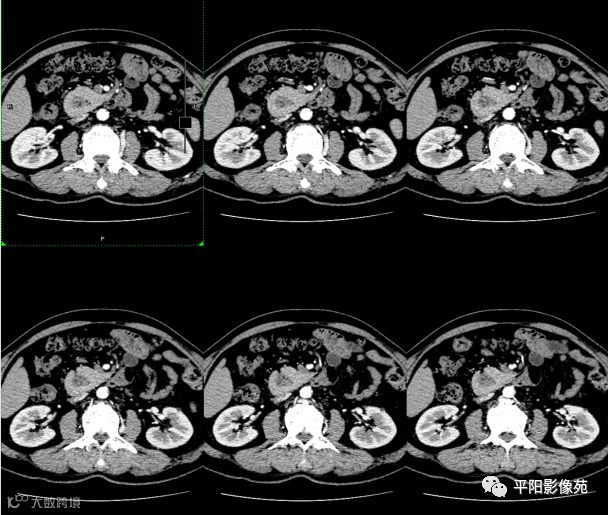

患者,男,49岁;

主诉:体检发现肝门淋巴结增大

影像表现:胰头环形包绕十二指肠降部

CT检查:主要征象为胰头部扩大,包绕十二指肠降段,导致十二指肠降段狭窄。增强扫描,胰腺组织明显强化,与十二指肠形成良好的对比。